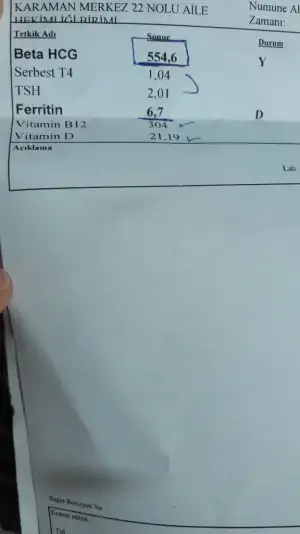

Doktorlarınız kan testi vs gibi testler istedi mi? İlk gebeliğimde epey ayrıntılı tahliller istemişti eski doktorum. Bu yeni doktora sorduğumda pek oralı olmadı da. Diğer kontrol için de 1 ay sonra gel bir sıkıntı olmadıkca dedi. Sağlık ocağına gidip yaptırayım diyorum kendi kendime bilemedim ne yapsam.